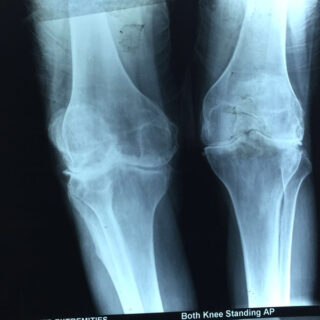

X-rays of patient of bilateral knee replacement in one sitting before and after surgery

Youngest Patient 39 years old Bilateral Total Knee Replacement done in one sitting.